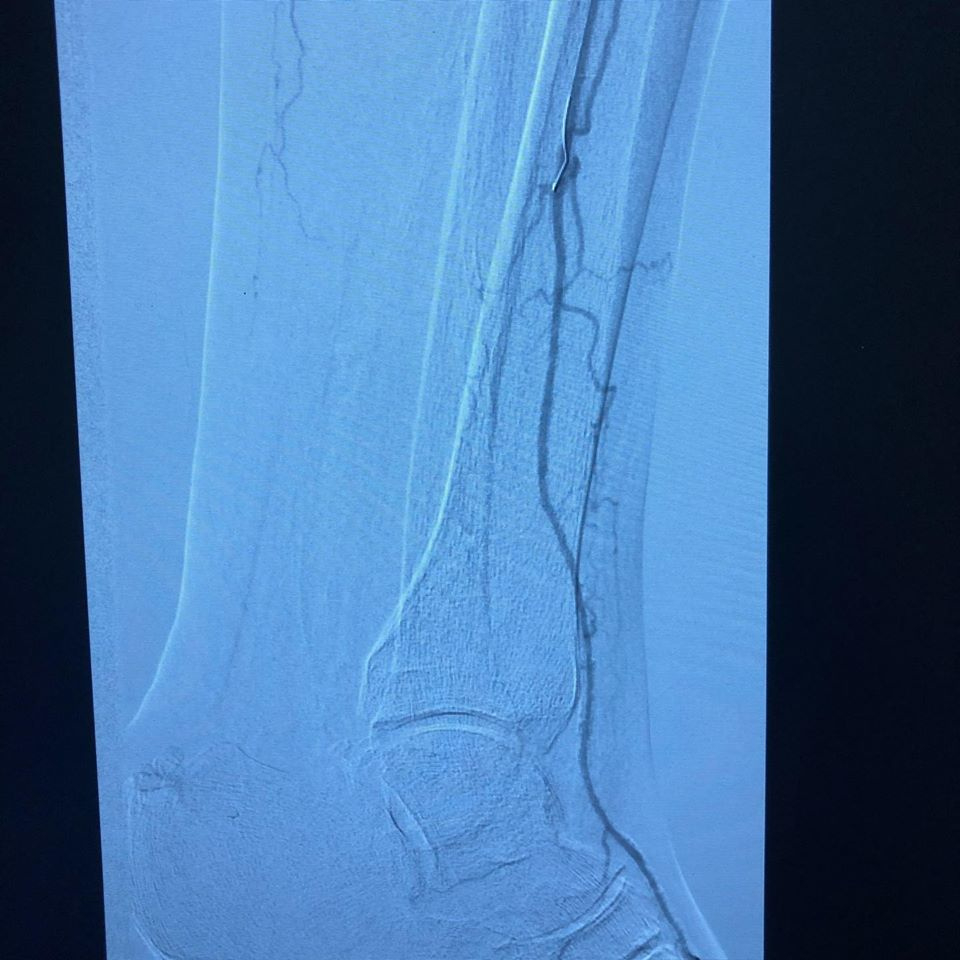

Se pasa a Hemodinamia donde se observa lesiones estenoticas en arteria poplitea y sin vasos tibiales, recanalizando en arteria pedía

(FP2, IP4, P2 GLASS 3) y se realiza angioplastia poplitea y de tibial anterior, mejorando el flujo distal, se realiza amputacion de falange distal del dedo y se observa buena evolución 24 hrs después sin complicaciones con alta a su domicilio